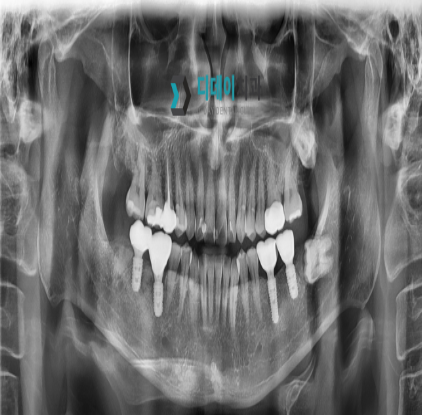

<전> 230622

<후> 240212

게시물의 치료 사진은 실제 본원에서 모든 치료 과정을 마친 환자분의 동의하에 촬영되었습니다. 전후 사진은 동일인이며, 동일 조건하에 촬영되었음을 밝힙니다.